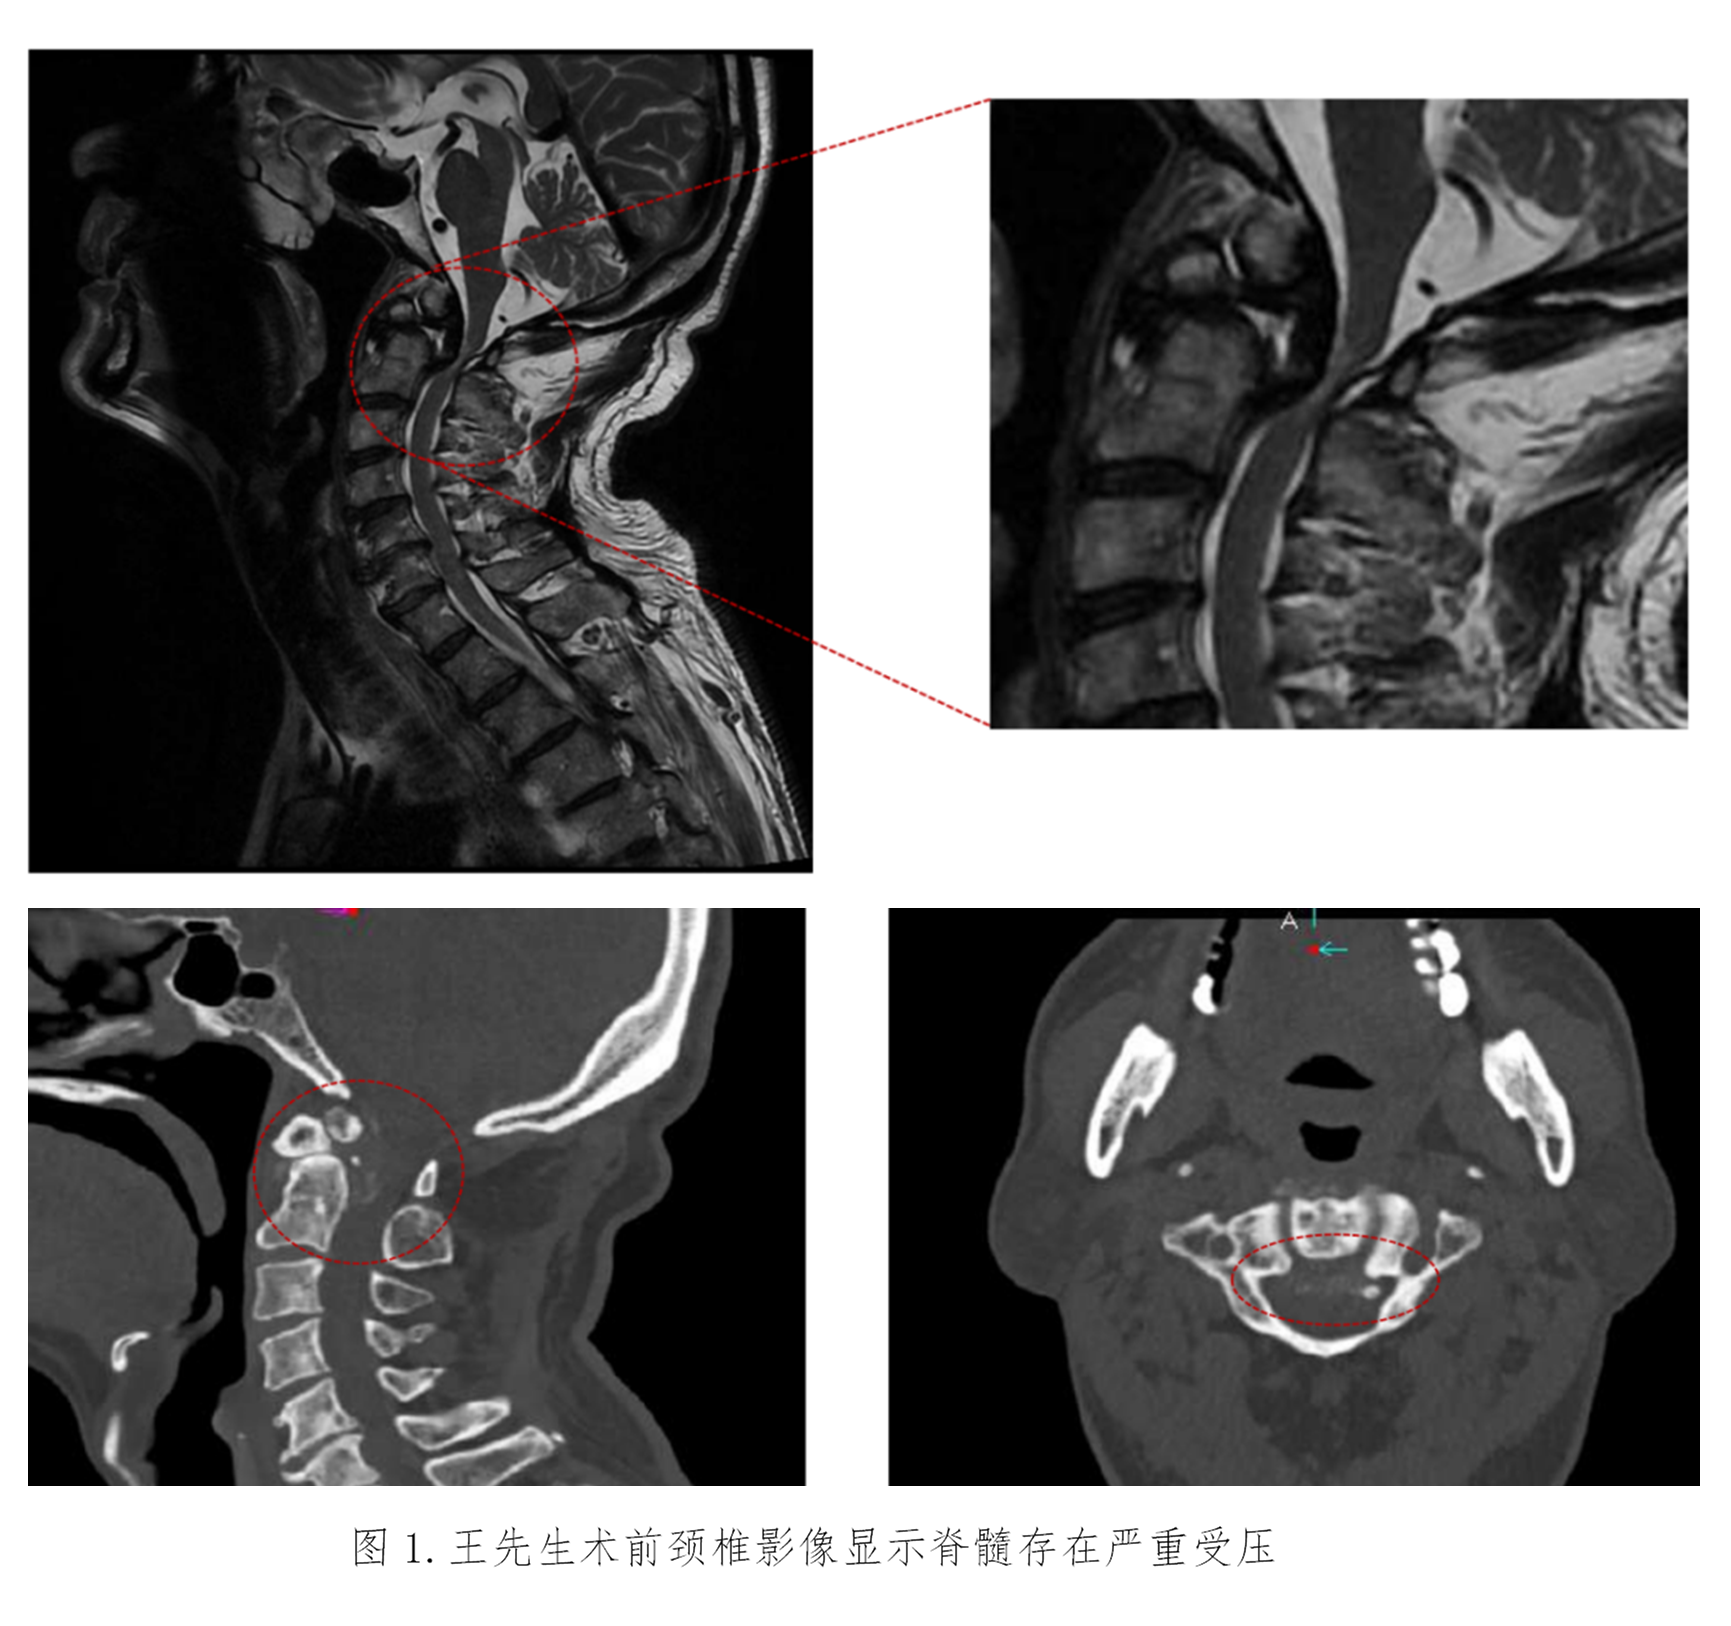

患者王先生已72岁,四肢乏力进行性加重10年,伴左下肢跛行4年,因担心需要手术治疗而没有正规就医。近期已无法独立行走,经推荐来到苏大附四院姜为民主任门诊就医。王先生的查体结果表现出明显的高位脊髓损伤症状:左上肢肌力下降至4级,左侧霍夫曼征、踝阵挛及巴彬斯基征均为阳性,左足下垂;右侧病情稍轻。影像学检查显示“游离齿状突畸形”——即第二颈椎(C2)齿状突发育异常并游离,后缘异常增生导致上段颈髓严重受压,脊髓功能受损使得患者近年来行走能力不断下降,并因此频繁跌倒,这对患者的生命安全构成了极大威胁。

颈椎手术尤其是上颈椎手术的难度与风险很高,常被誉为刀尖上的舞蹈。术前的全面检查显示,该例患者与常见的上颈椎游离齿突畸形不同——引起颈髓损伤的主要原因不是寰枢椎不稳,而是齿突后方的异常骨性增生严重压迫脊髓所致。目前常用的手术解除脊髓压迫方法是经口咽途径直接切除游离的齿突及增生的骨性结构,再从后方行枕颈固定融合。但是这种手术不仅难度高而且有大量并发症风险,更是会令患者失去头部旋转功能的风险。最初姜主任团队一度考虑采用该常规手术方案,但对于这位72岁的高龄患者而言,创伤与风险是巨大的。